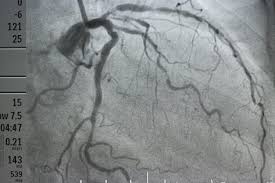

How Do I Know If I Have Clogged Arteries - A complete blockage can cause a heart attack.

How Do I Know If I Have Clogged Arteries - A complete blockage can cause a heart attack.. How to identify symptoms of clogged arteries? Coronary artery disease can lead to: This can cause chest pain (angina) or shortness of breath. A tight jaw, one of the symptoms of clogged arteries, occurs more often in women, but men should be aware of it, too. The coronary arteries supply blood, oxygen and nutrients to your heart.

Sometimes, when arteries become completely blocked, a new blood supply develops around the blockage.

Feeling suddenly hot and sweating is a sign of clogged arteries and may also be a precursor to a heart attack. While you may have no obvious signs early on, symptoms can develop as plaque builds up in the arteries. If the plaque surface breaks or ruptures, blood cells called platelets clump together at the site to try to repair the artery. Coronary artery disease is thought to begin with damage or injury to the inner layer of a coronary artery, sometimes as early as childhood. The amount of damage depends in part on how quickly you receive treatment. Control conditions such as high blood pressure, high cholesterol and diabetes. See full list on wikihow.com A doctor will answer in minutes.

Not being active (sedentary lifestyle) once the inner wall of an artery is damaged, fatty deposits (plaque) made of cholesterol and other cellular waste products tend to collect at the site of injury. Coronary artery disease develops when the major blood vessels that supply your heart become damaged or diseased. Breathing in secondhand smoke also increases a person's risk of coronary artery disease. But you can take steps to prevent and treat coronary artery disease. The damage may be caused by various factors, including: Jul 09, 2018 · sweating: Coronary artery disease is thought to begin with damage or injury to the inner layer of a coronary artery, sometimes as early as childhood. A healthy lifestyle can make a big impact.